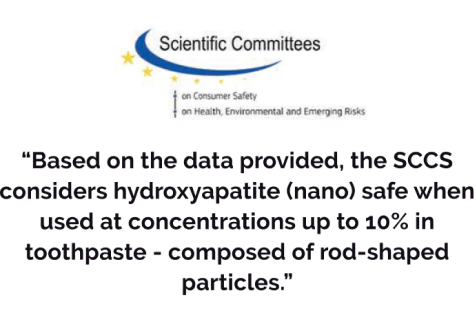

Formulated with 10% nano Hydroxyapatite, 0.22% fluoride, and Xylitol, Dr. Jen's Super Paste offers a powerful combination that strengthens enamel, fights cavities, and supports overall oral health.

Safe enough to use just like your OTC toothpaste, Dr. Jen's Super Paste provides superior benefits of high prescription toothpaste without the associated risks.

Triple proven ingredients with 10% nano Hydroxyapatite, fluoride, xylitol

Our Top Pick toothpaste for remineralization is Dr. Jen Super Paste Natural Remineralizing Toothpaste. Dr. Jen contains fluoride (as 0.22% sodium fluoride) as well as 10% nano-hydroxyapatite, and, as discussed earlier, this combination has been shown in laboratory research to promote remineralization of enamel better than fluoride alone.